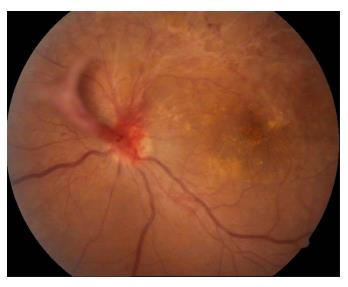

患者女,2 3岁,既往高血压病病史,因“左眼视物模糊1 3天”于2011年4月1 5日就诊于济宁医学院附属医院眼科,眼科查体:右眼视力为0.6,左眼视力为0.08,双眼眼前节情况正常,右眼眼底动脉反光增强,静脉略迂曲(图1),左眼眼底颞上方视网膜大片火焰状出血、棉绒斑、静脉迂曲、黄斑水肿(图2 )。眼底荧光血管造影示:左眼颞上方网膜大片荧光遮蔽,微血管瘤,未见明显无灌注区(图3 ),诊断“左眼视网膜分支静脉阻塞,双眼高血压视网膜病变”,给予随访观察,控制血压。发病36 d时,眼底检查见:左眼视盘新生血管(图4);眼底血管造影检查见:左眼视盘荧光渗漏,颞上视网膜大片无灌注区(图5),给予眼底病变区视网膜激光光凝治疗。发病75 d时,眼底检查见:左眼视盘新生血管增殖膜,颞上方视网膜血管闭塞,散在激光斑(图6,7 ),补充病变区激光治疗。发病103 d时,眼底血管造影检查见:左眼视盘荧光渗漏,颞上方视网膜异常血管网(图8,9 ),补充病变区激光治疗。发病138 d时,左眼视力为0.02,视盘形成新生血管膜,表面血管旺盛(图1 0,11),再次补充病变区激光治疗。1 0年后因“右眼视力下降3天”就诊,查体:右眼视力为0.4,左眼视力为0.4;眼底检查见:左眼视盘新生血管膜机化萎缩,表面无血管(图12),右眼后极部颞下、颞上视网膜棉绒斑,鼻下和鼻侧视网膜浅层出血,鼻上视网膜少许硬性渗出(图13)。

20230106112733_6138.jpg

图4 左眼眼底彩照见颞上方网膜大片火焰状出血,静脉迂曲,黄斑区可见渗出,视盘新生血管(发病36 d)

Figure 4 Color fundus of the left eye showed large flaming hemorrhage and tortuous veins of the supratemporal retina, exudation of the macula, the neovascularization of the optic disc (oneset of 36 d)